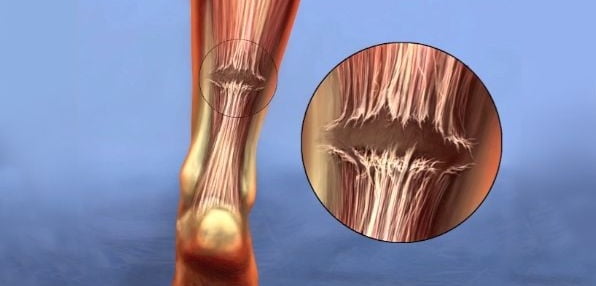

تاندون، یک بافت فیبری است که عضلات را به استخوان در بدن انسان متصل میکند. نیروهایی که بر تاندون وارد میشوند، ممکن است بیش از ۵ برابر وزن بدن باشند. در برخی موارد نادر، تاندونها ممکن است پاره شوند. برخی از بیماریها میتوانند عاملی برای پاره شدن تاندونها باشند، از جمله تزریق استروئید در تاندون، بروز برخی بیماریها مانند نقرس یا هایپرپاراتیروئید و همچنین داشتن گروه خونی O.

- درجه ۲: تاندون به طور جزئی دچار پارگی شده است اما برخی فیبرهای تاندون سالم باقی ماندهاند.

- درجه ۳: تاندون به طور کامل پاره شده است.

معمولاً تاندون آشیل از حدود ۶ سانتیمتر بالای استخوان پاشنه پا، پاره میشود. گردش خون در این قسمت ضعیف بوده و بافتهای فیبری در این قسمت آسیبپذیرتر هستند.